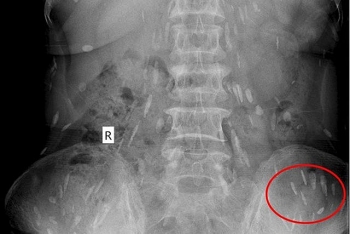

• Một phụ nữ ở Nghệ An bị sán lá gan ký sinh hầu hết bộ phận trong cơ thể

Một phụ nữ ở Nghệ An bị sán lá gan ký sinh hầu hết bộ phận trong cơ thể

(PetroTimes) - Bệnh viện Quốc tế Vinh mới đây vừa tiếp nhận một nữ bệnh nhân bị đau đầu, đau ở vùng ngực, thắt lưng, mệt mỏi kéo dài.